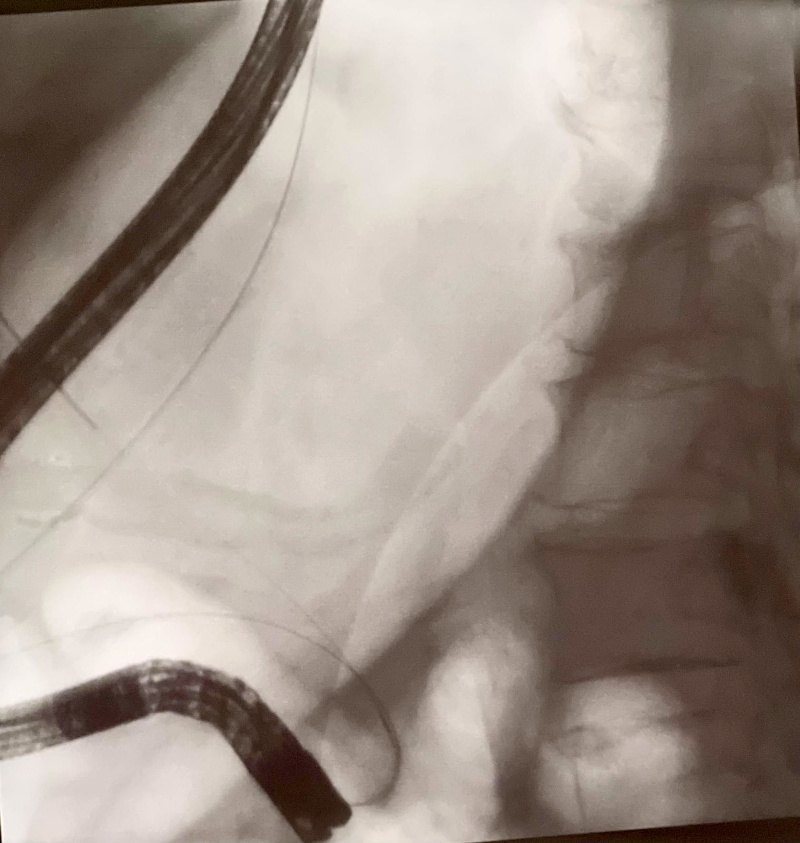

Incannulamento profondo della via biliare

principale dopo rendez-vous

Il caso riguarda una signora di 75 anni, ricoverata per colangite acuta sostenuta da un calcolo nel coledoco, un condotto tra il fegato e l’intestino. La paziente era stata indirizzata a procedura “ERCP”, colangio-pancreatografia endoscopica retrograda, finalizzata alla rimozione del calcolo. Purtroppo, la via biliare principale non è risultata accessibile nonostante i diversi tentativi effettuati, a causa della particolare conformazione della papilla, dura e fibrotica. A quel punto, gli specialisti dell’unità operativa coordinata dal dott. Santo Grasso hanno deciso di portare a termine la procedura con un intervento endoscopico combinato chiamato “Rendez Vous”: «Si tratta di una metodica – spiega il dott. Grasso – che utilizza l’ecoendoscopia in una prima fase, per visualizzare e ottenere l’accesso del filo-guida nella via biliare, e una ERCP convenzionale in una seconda fase, per effettuare la bonifica della via biliare stessa. La paziente ha potuto ricevere un trattamento completo in un unico tempo, con un’unica anestesia, evitando così interventi alternativi di tipo percutaneo o chirurgico e i possibili conseguenti rischi di eventi avversi e allungamento della degenza ospedaliera». La signora ha risposto ottimamente al trattamento ed è stata dimessa nel giro di pochi giorni.